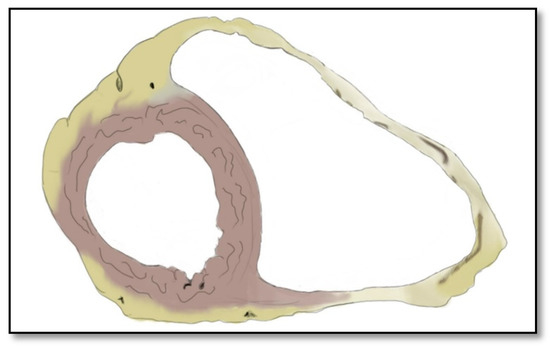

- Intramyocardial adipose tissue disposition—”obsolete”Although intramyocardial fat has long been a diagnostic criterion for ARVC, it is no longer used because other pathological or physiological conditions can lead to this appearance in cardiac MRI. In normal people, epicardial fat can penetrate to the myocardium and endocardium, with no clear demarcation between the epicardium and the myocardium, leading to misinterpreted images as ARVC. When intramyocardial fat is detected, it will be considered pathological only if it is associated with contraction abnormalities of the corresponding wall [12,45].Fat in ARVC appears as hyperintense intramyocardial signal at T1 spin-echo. Adipose tissue infiltrates mainly the RVOT, the free wall of the right ventricle, the intracavitary trabeculae, the moderating band, and the right side of the interventricular septum (Figure 4).Tansey et al. showed on autopsies of individuals without known heart disease that 85% of them had myocardial infiltrates with adipose tissue [46]. Mainly, the RVOT, free wall of RV wall, apex, and RV antero-lateral wall are affected, but these intramyocardial deposits do not change the thickness of the ventricular wall or the regional contraction. If the deposits extend from the epicardium to the endocardium, crossing the myocardium, then the ventricular wall may increase in size as a normal feature of the adipose distribution. It seems that these fat deposits in healthy people increase with age and are more common in obese people without being pathological [47].